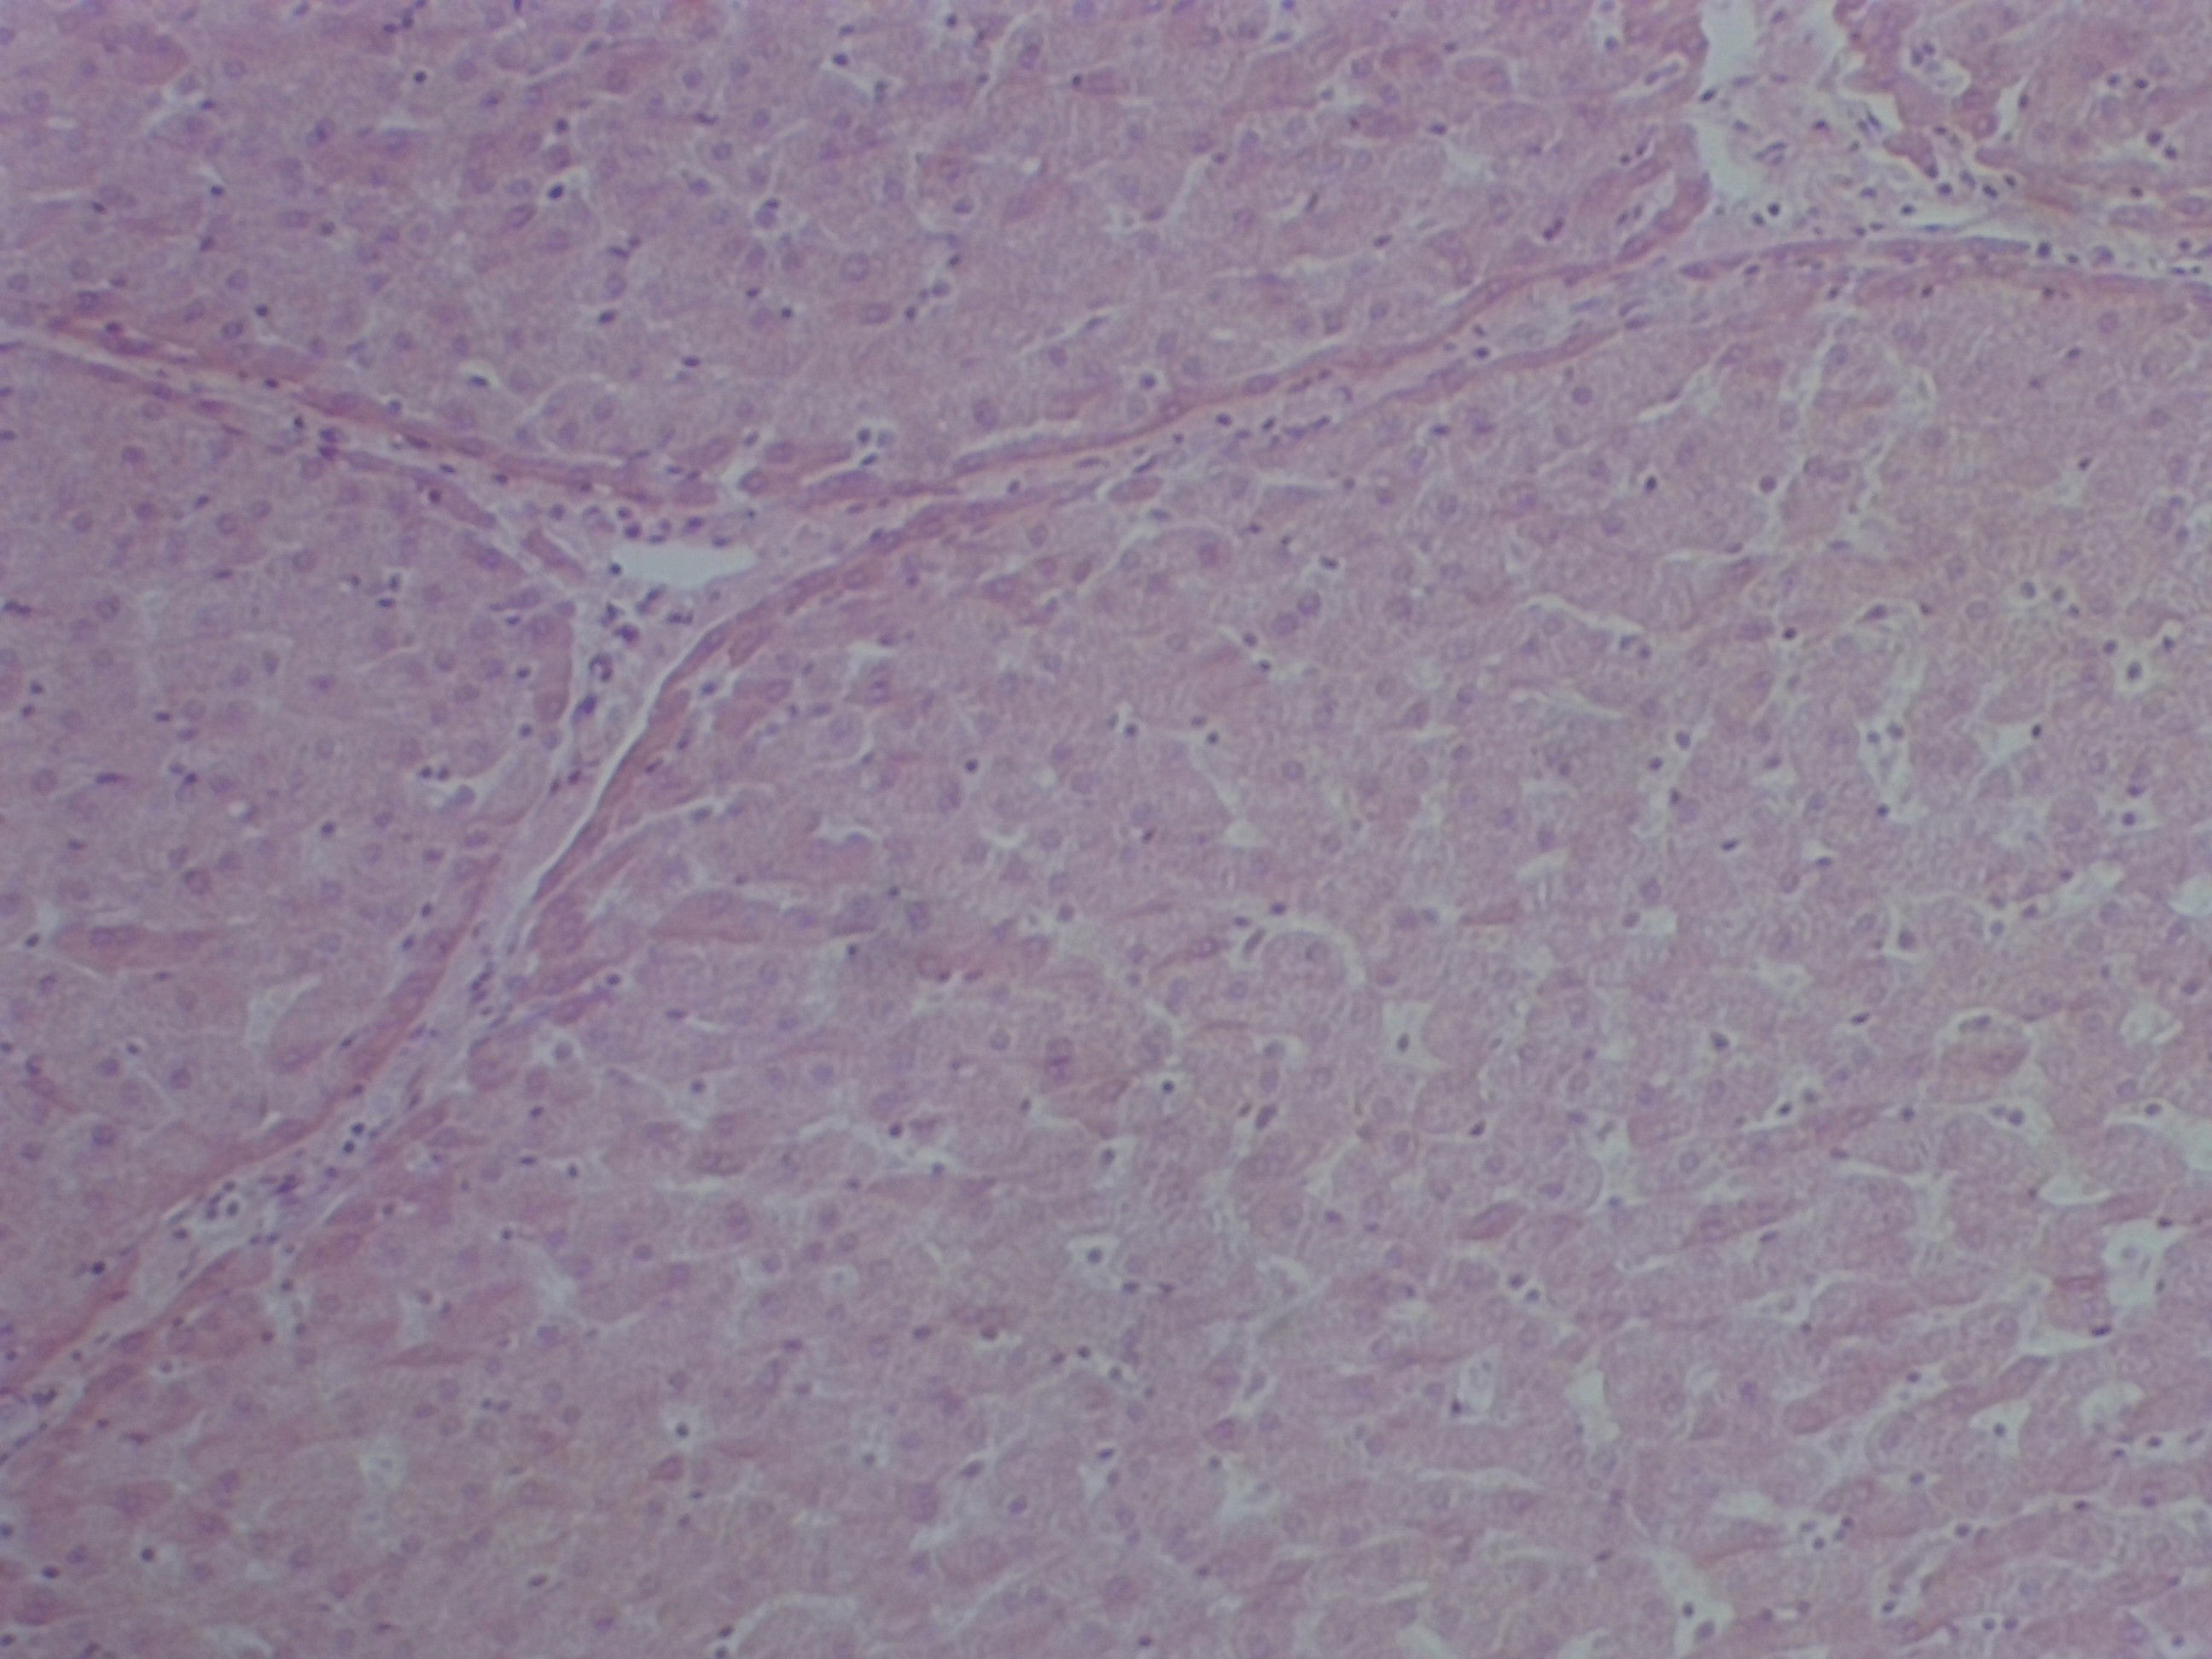

• Liver Tissue